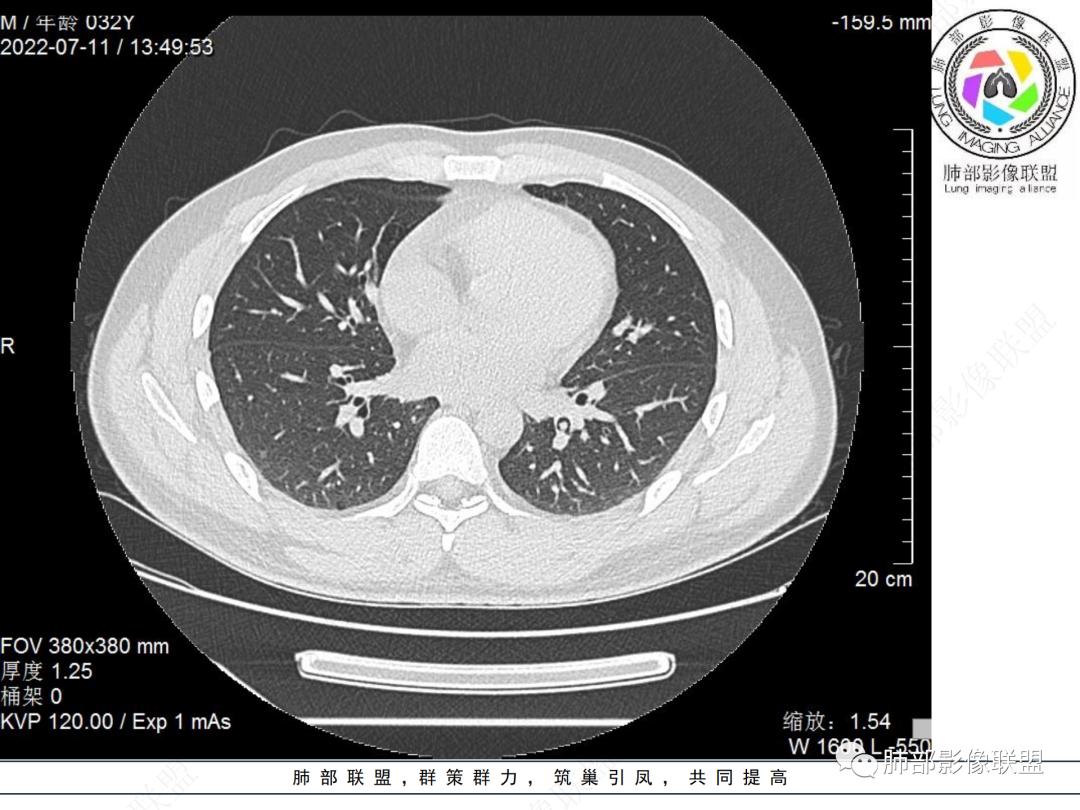

左肺下叶后基底段开口处结节,边缘光滑清楚,没有增强扫描,年轻男性患者痰血三天,考虑1.良性病变:腺瘤、错构瘤、平滑肌瘤

2.恶性:类癌、粘液表皮样癌。

左肺下叶外后基底段气管内见结节状影,边缘部分清晰。考虑错构瘤,待排恶性病变。

左肺下叶气管内外占位病变,咯血病史,考虑类癌,粘表待排。

青年男性,左肺下叶后基底段支气管开口软组织结节,边缘光整,气管镜提示质软,易出血,考虑类癌

左肺下叶后基底段开口处结节,边缘光滑清楚,年轻患者考虑鳞癌或腺样囊腺癌

左肺下叶气道腔内占位,远端无花花草草,疾病谱:鳞,类癌,粘表,腺样囊腺癌,小,无增强,不好判断,临床咯血,选类癌。

大支气管腔内结节,考虑类癌

左肺下叶后基底段开口处结节影,边缘光滑,患者年龄较小,首选类癌

男性,咳血左肺下叶支气管腔内结节影,没有阻塞性炎症,考虑类癌,鳞癌

年轻男性,支气管内结节,首先类癌

左肺下叶后基底段开口处腔内见壁结节,花生米样,宽基底,补充增强及矢状位重建,确定我无向壁外突破浸润生长,另见强化的特点,临床触之易出血,类Ca可能性大。

年轻男性,支气管腔内占位,边缘尚平整,年轻人,首先类癌,鉴别错构

年轻男性,咳血,左肺下叶后基底段支气管腔内结节,边缘光滑,首先考虑青年三件套,类癌大于粘液表皮样癌,支气管镜质软,触之易出血,鉴别血管瘤,平滑肌瘤

左肺下叶后基底段开口部结节,密度较均匀一致,边缘较光整,目测密度偏低,支气管镜示:质软、触之易出血,考虑恶性,类癌。

支气管腔内结节,有蒂与支气管壁连接,考虑良性病变可能性大,支气管错构瘤  血管瘤一类的

左肺下叶后基底段支气管腔内结节,有蒂,容易出血,先考虑良性病变,肉芽组织型血管瘤,与类癌鉴别。

青年男性,左肺下叶后基底段支气管开口软组织结节,边缘光整,气管镜提示质软,易出血,考虑恶性类癌

左肺下叶后基底段开口处结节影,边缘光整,年轻患者,伴咯血,考虑鳞癌,类癌不能排除